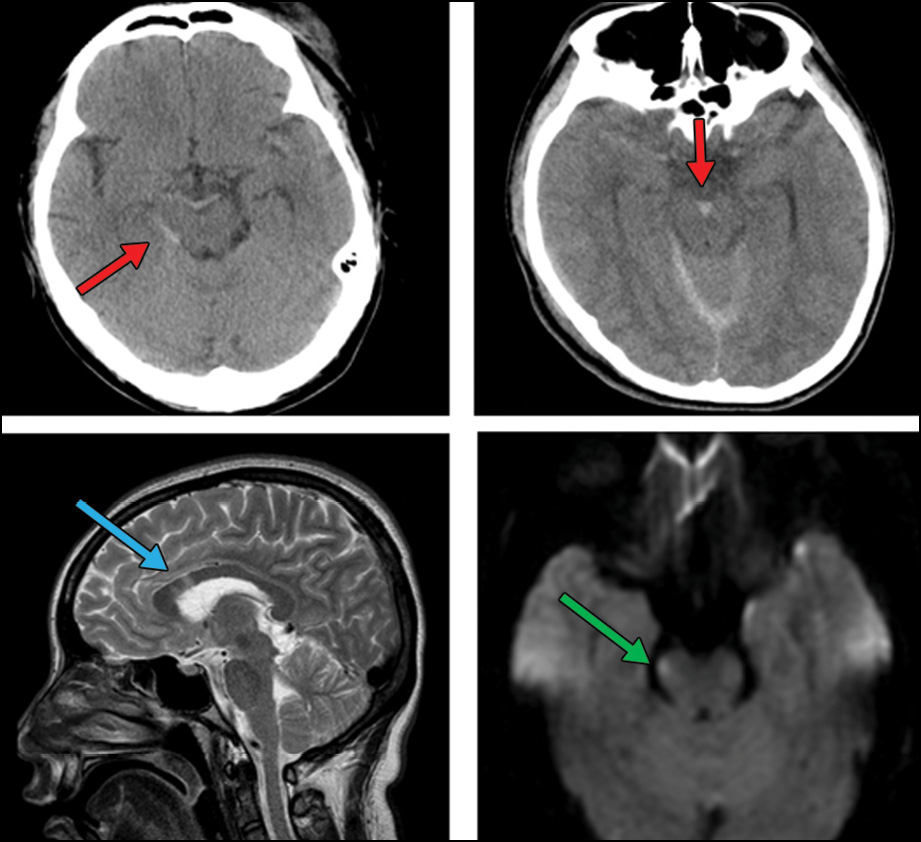

An image from Dr. Mbemba's research showing the initial CT performed 50 minutes after onset showed the presence of midline (perimesencephalic) subarachnoid hemorrhage

An image from Dr. Mbemba's research showing the initial CT performed 50 minutes after onset showed the presence of midline (perimesencephalic) subarachnoid hemorrhage (red arrows), which predicted the presence of severe DAI [DAI located in the corpus callosum (blue arrow) or in the brainstem (green arrow)] as shown on subsequent MRI performed 3 days later.